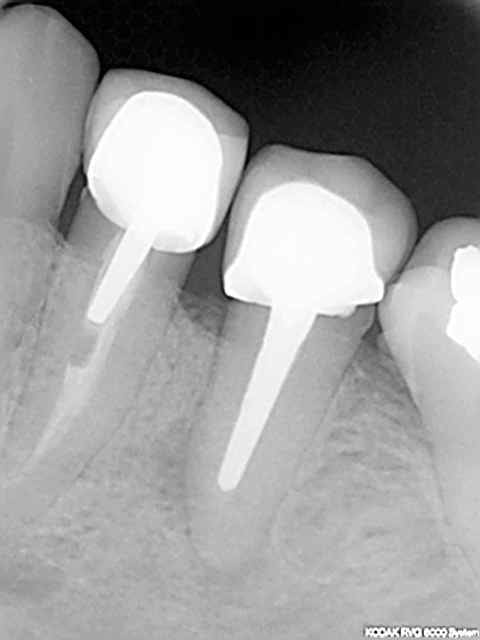

Plus sérieusement sur le premier cas le foret en place est le terminal de 12x3,5, je le trouve pas si mal l'axe 3d, mais j'ai un peu forcé sur le biomat

pour l'autre cas, je suis aussi dans l'axe,j'avais décalé le deuxieme forage en palatin pour faire une expansion

vesti, puis j'ai choisi la facilité

Olivier et les autres, pouvez-vous détailler ce qui dans le positionnement 3D a amené un tel échec esthétique?

Je dirai un axe vestibulo-palatin trop incliné en vestibulaire, mais est-ce la seule cause?

>Je dirai un axe vestibulo-palatin trop incliné en vestibulaire, mais est-ce la seule cause?<

Désolé, mais le résultat des couronnes secteurs 2 sur implants n'est pas tès intéressant...et je crois que l'axe est en cause...